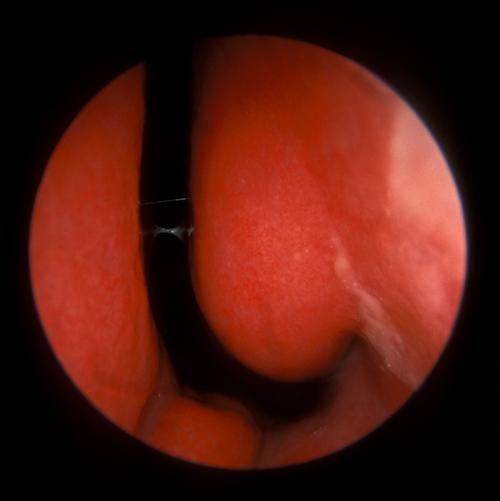

相关图片